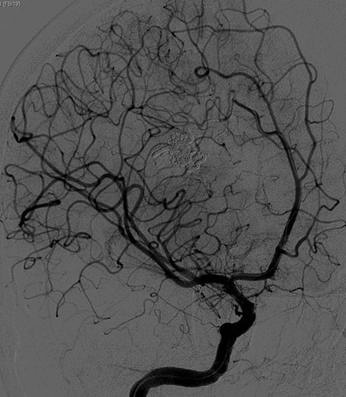

Париетальная АВМ, закрытая в один этап

Первичная ангиография

Завершение процедуры – полная окклюзия АВМ